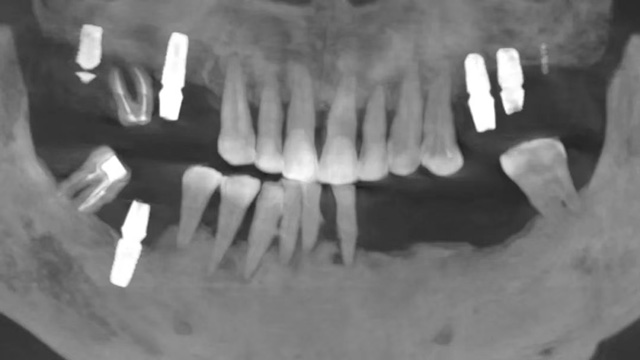

據(jù)新橋口腔成都蜀漢院區(qū)種植??浦魅谓浇榻B,張先生的口腔情況較為復(fù)雜:之前種植的6顆種植牙牙冠全部脫落,只剩下種植體,其中一顆種植體已折斷,還有兩顆牙做過(guò)根管治療,其中一顆牙冠脫落,此外,他口腔里還存在多顆牙齒缺失和松動(dòng)等問(wèn)題。

張先生10年前種下的6顆種植牙牙冠全部脫落

經(jīng)過(guò)詢問(wèn),醫(yī)護(hù)人員得知張先生當(dāng)年種完牙后,還沒(méi)等到佩戴正式牙冠就離開(kāi)成都了,他花“巨資”種下的6顆牙這么多年來(lái)只有臨時(shí)牙冠。“臨時(shí)牙冠是作為過(guò)渡使用的材料,在硬度、咬合、穩(wěn)定性等方面都比不上正式的牙冠,影響到了種植牙的正常使用壽命。”牙冠脫落后,張先生繼續(xù)使用僅剩下“光桿”的種植體進(jìn)行咀嚼,最終導(dǎo)致種植體受損,發(fā)生折斷、松動(dòng)等情況。